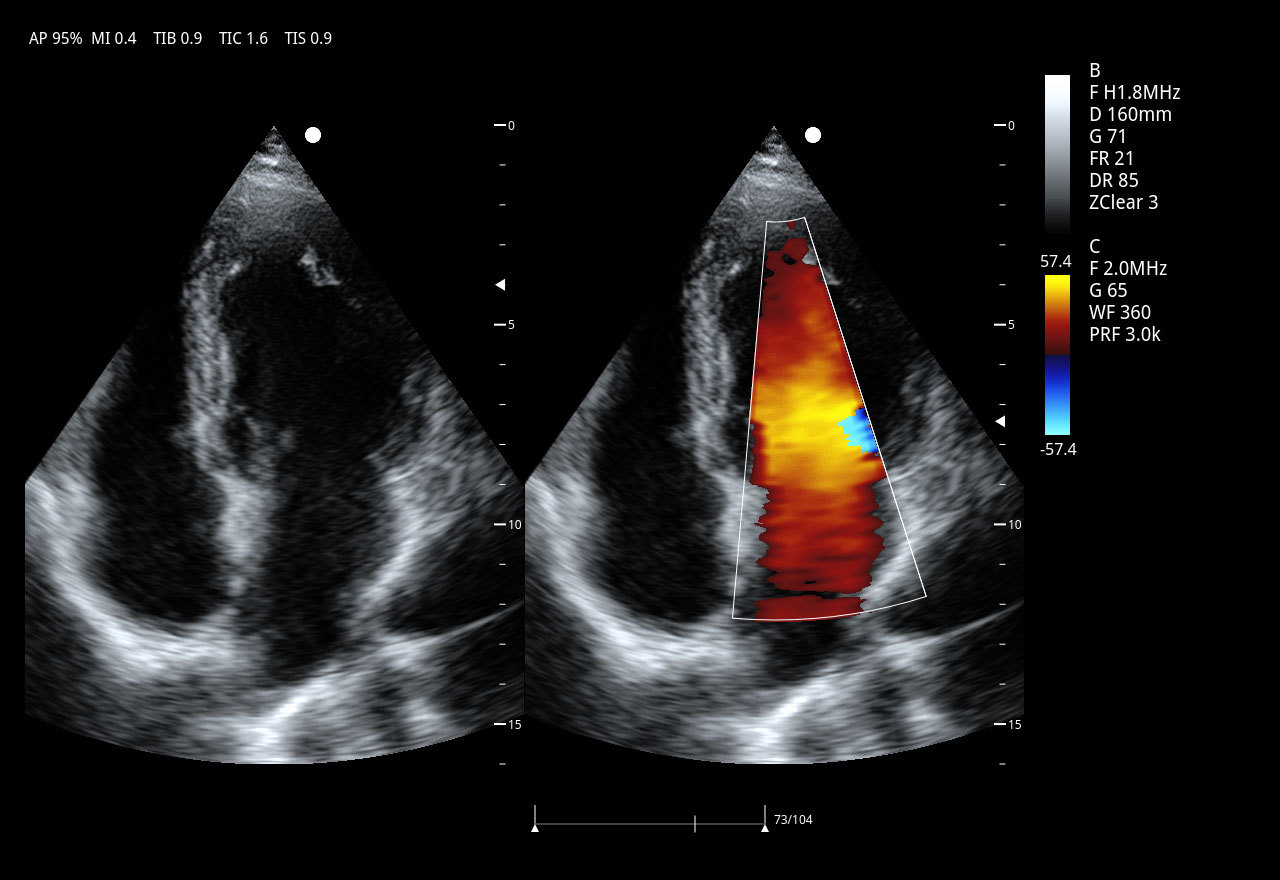

Imágenes clínicas extraordinarias

| Aplicaciones | Cardiología, abdomen, vasos sanguíneos, estudios generales |